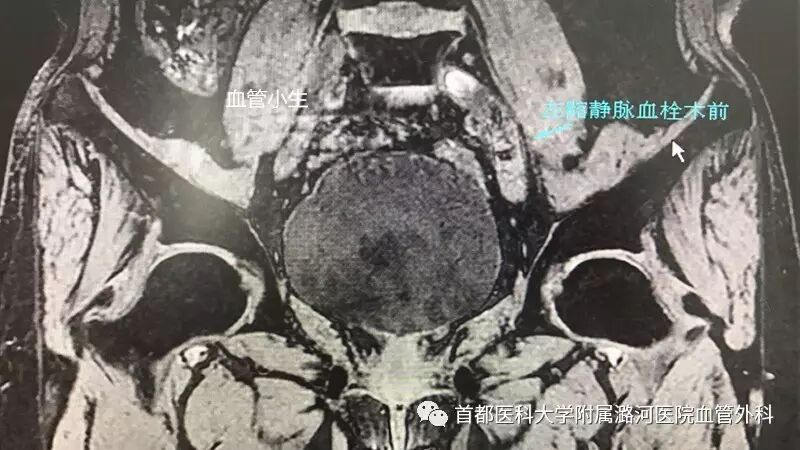

下肢MRV:

下肢静脉核磁:

随着临床工作的逐渐开展,相关科室的逐渐认识,发现确诊髂静脉越来越简单。